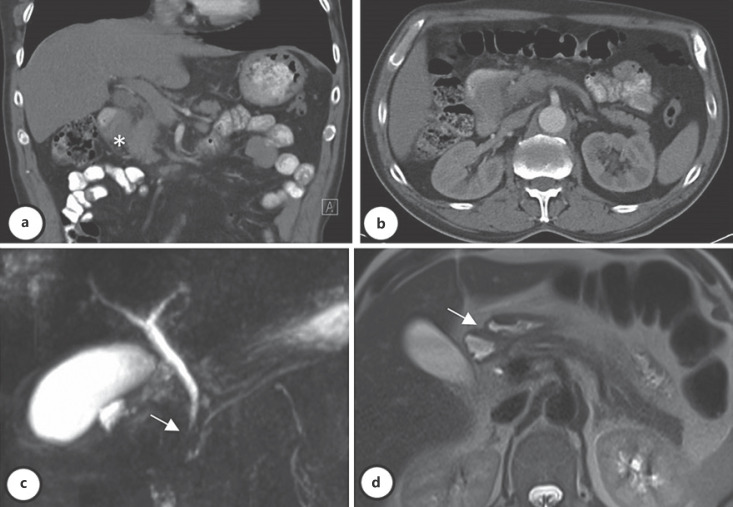

Introduction: Groove pancreatitis (GP) is a type of chronic segmental pancreatitis that affects the pancreatoduodenal groove area, and it is often misdiagnosed. Outflow obstruction of the minor papilla associated with alcohol consumption seems to be the main pathophysiological mechanism, and it affects mainly middle-aged males. Symptoms include nausea and postprandial vomiting from gastric outlet obstruction, weight loss, and abdominal pain. Despite modern advances, such as radiological and endoscopic methods, distinction between GP and pancreatic cancer remains a challenge, and histological examination is sometimes necessary. When a diagnosis can be obtained without a surgical specimen, management can be conservative in the absence of acute or chronic complications.

Case presentation: The authors present 2 clinical cases which portray the diagnostic workup and management decisions of this entity.

Discussion/conclusion: GP is a clinical entity, offering diagnostic and therapeutic challenges. Imaging exams are crucial in the diagnosis and follow-up, but surgery may be necessary in a significant number of cases due to the incapacity to rule out malignancy.